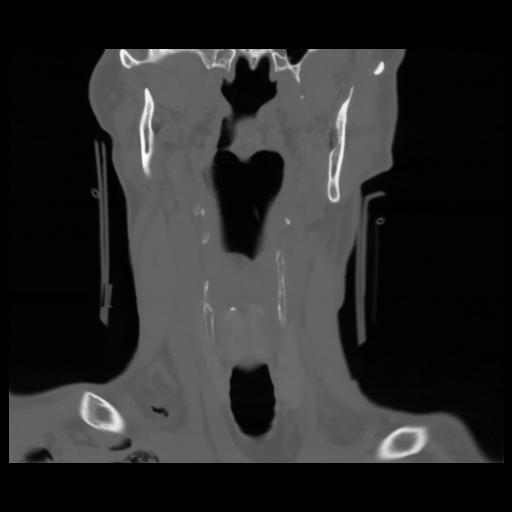

13 P.BLANDAS,,Coronal,2.000,P.BLANDAS,Coronal,